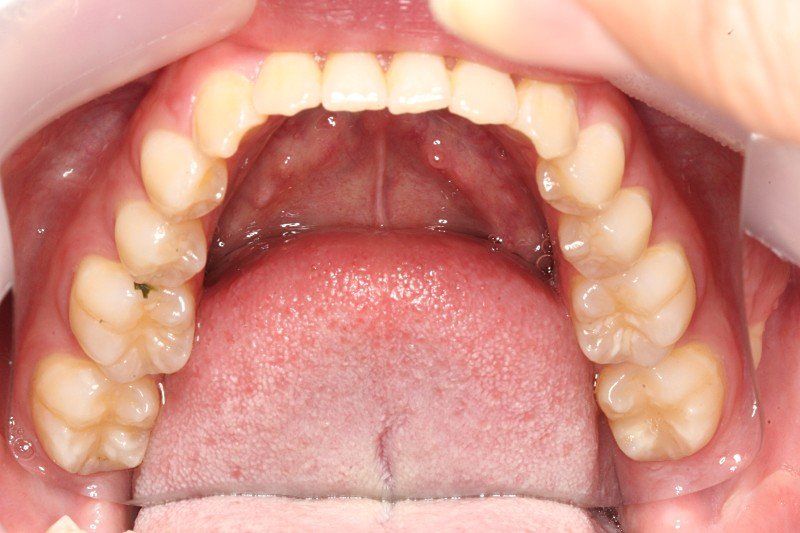

약간 비대칭이 있긴한데... 치아중심선 맞추기랑 앞니 부분적으로 절단교합이 있어서 교정할려고 해요

인비절라인으로 하면 1년 정도면 된다고 하는데 투명교정 하게되면 치아중심선이랑 12번치아 앞니 교합 교정, 전체적 치아가 살짝 틀어진거 교정 효과 볼 수 있을까요?

• 2번 째 사진